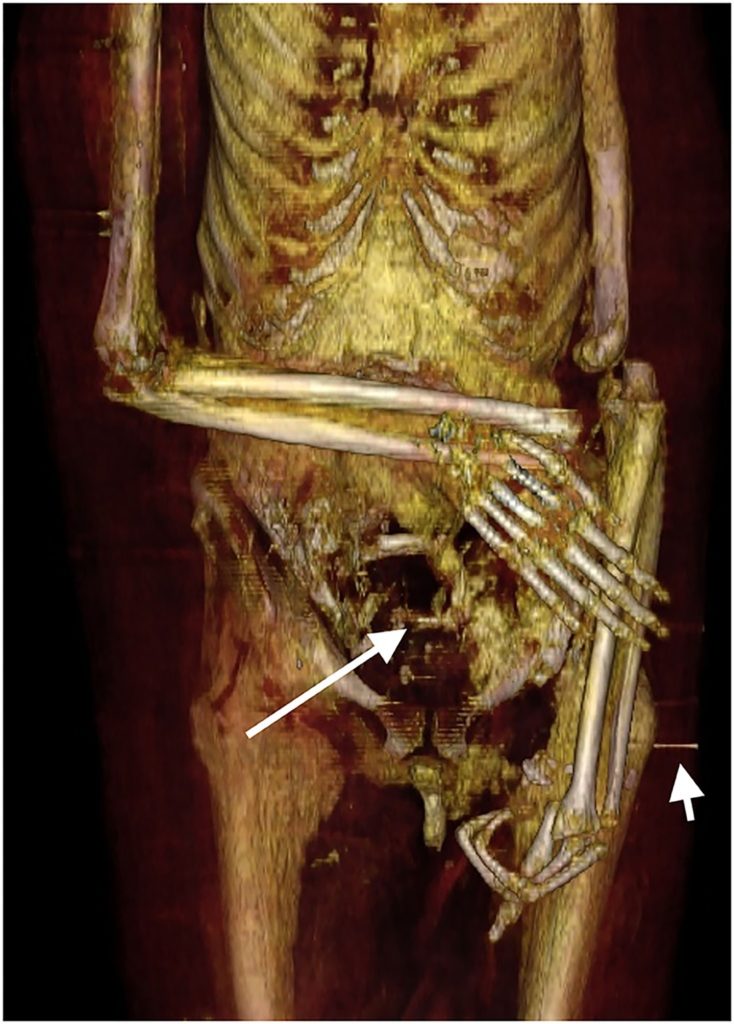

Mystery remains concerning the death of Amenhotep. CT scans revealed no “wounds or disfigurement due to disease to justify the cause of death,” said Saleem, who found “numerous mutilations post mortem, presumably by grave robbers after his first burial.”

Most of Amenhotep’s entrails were removed, though his heart remained customarily untouched since the organ was thought to be the seat of one’s soul.

The robberies had done enough damage to the Amenhotep’s body that it had to be re-mummified during the 11th century BC.

“We show that at least for Amenhotep I, the priests of the 21st dynasty lovingly repaired the injuries inflicted by the tomb robbers, restored his mummy to its former glory and preserved the magnificent jewelry and amulets in place,” said Saleem.